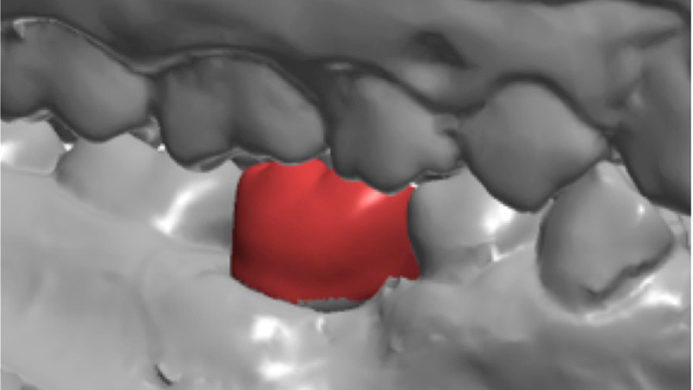

“Ideal regeneration starts from the ‘science of space management’ “

Clinical case: # 46 implant placement & GBR using i-Gen membrane for significant vertical resorption & mixed bone defect

- Courtesy of Dr. Iulian Filipov, Romania -